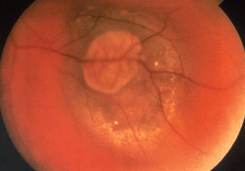

По мере роста меланомы она приобретает правильную полушаровидную форму, на ее поверхности появляются пятна оранжевого пигмента, которые обусловлены отложением липофусцина в пигментном эпителии сетчатки (см. рис. 23 на цветной вклейке). На поверхности опухоли видны широкие извитые новообразованные сосуды. Ретинальные сосуды над опухолью уплощаются. На поверхности опухоли появляются кровоизлияния. Увеличивается вторичная отслойка сетчатки. Иногда формируется так называемая ;грибовидная ;форма опухоли (см. рис. 24, 25 на цветной вклейке). Такая опухоль имеет довольно широкое основание, узкий перешеек и шаровидную головку. Головка опухоли нередко прорастает сетчатку и тогда в стекловидном теле можно видеть взвесь опухолевых клеток. Из новообразованных сосудов опухоли возникают субретинальные кровоизлияния с последующим развитием ;гемофтальма.

Рисунок 23. Меланома хориоидеи в нижненаружном квадранте глазного дна. На поверхности опухоли видны пятна оранжевого пигмента

Рисунок 24. Грибовидная форма меланомы хориоидеи

Рисунок 25. Энуклеированный глаз. Видна грибовидная форма меланомы хориоидеи